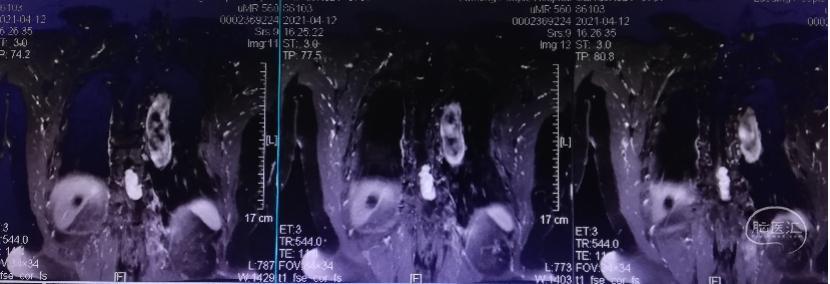

术前影像及分析:患者以双下肢麻木,神经根痛就诊,合并有脊柱侧弯,胸椎压缩骨折,脊柱稳定性条件差。MRI发现椎管内肿瘤累及胸椎3个节段,肿瘤约4.2x2cm大小,胸髓严重受压移位。胸椎椎管容积小,肿瘤偏大,多个节段受累,因此病变显露可能需要全椎板入路,重建脊柱稳定。手术指征明确,拟采用后正中入路椎管肿瘤切除术+胸椎内固定术。

矢状位:肿瘤呈椭圆形,均匀强化

冠状位:肿瘤偏左侧

轴位:脊髓受压扁薄